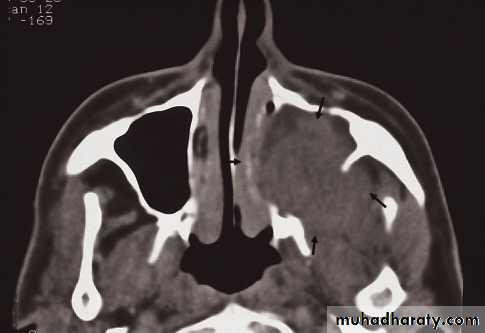

Mucosal thickening and a fluid level

• The causes of an opaque sinus are:

• Infection or allergy.

• Mucocele.

• Carcinoma of the sinus or nasal cavity.